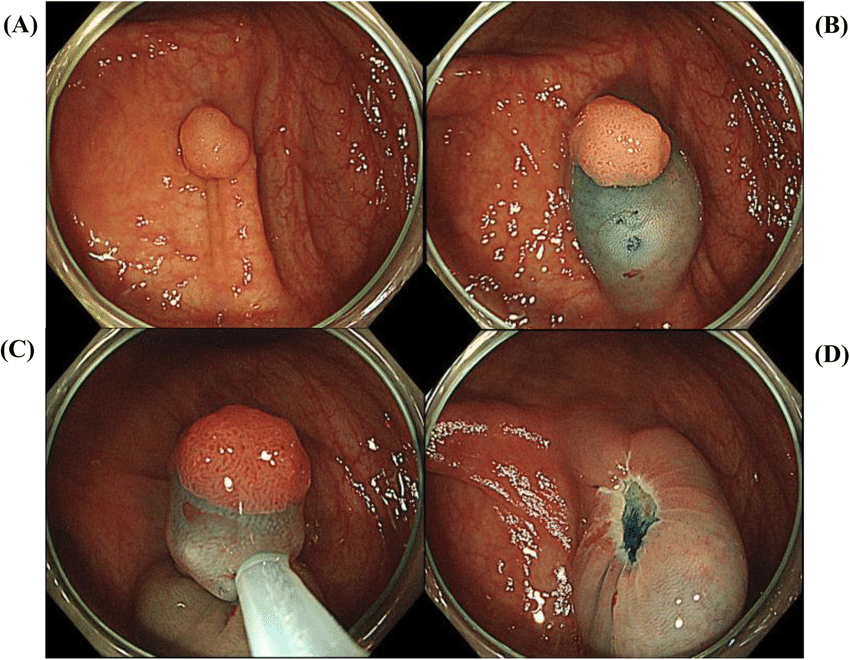

A specialized procedure used to diagnose and treat disorders of the bile ducts and pancreas. Common indications include: